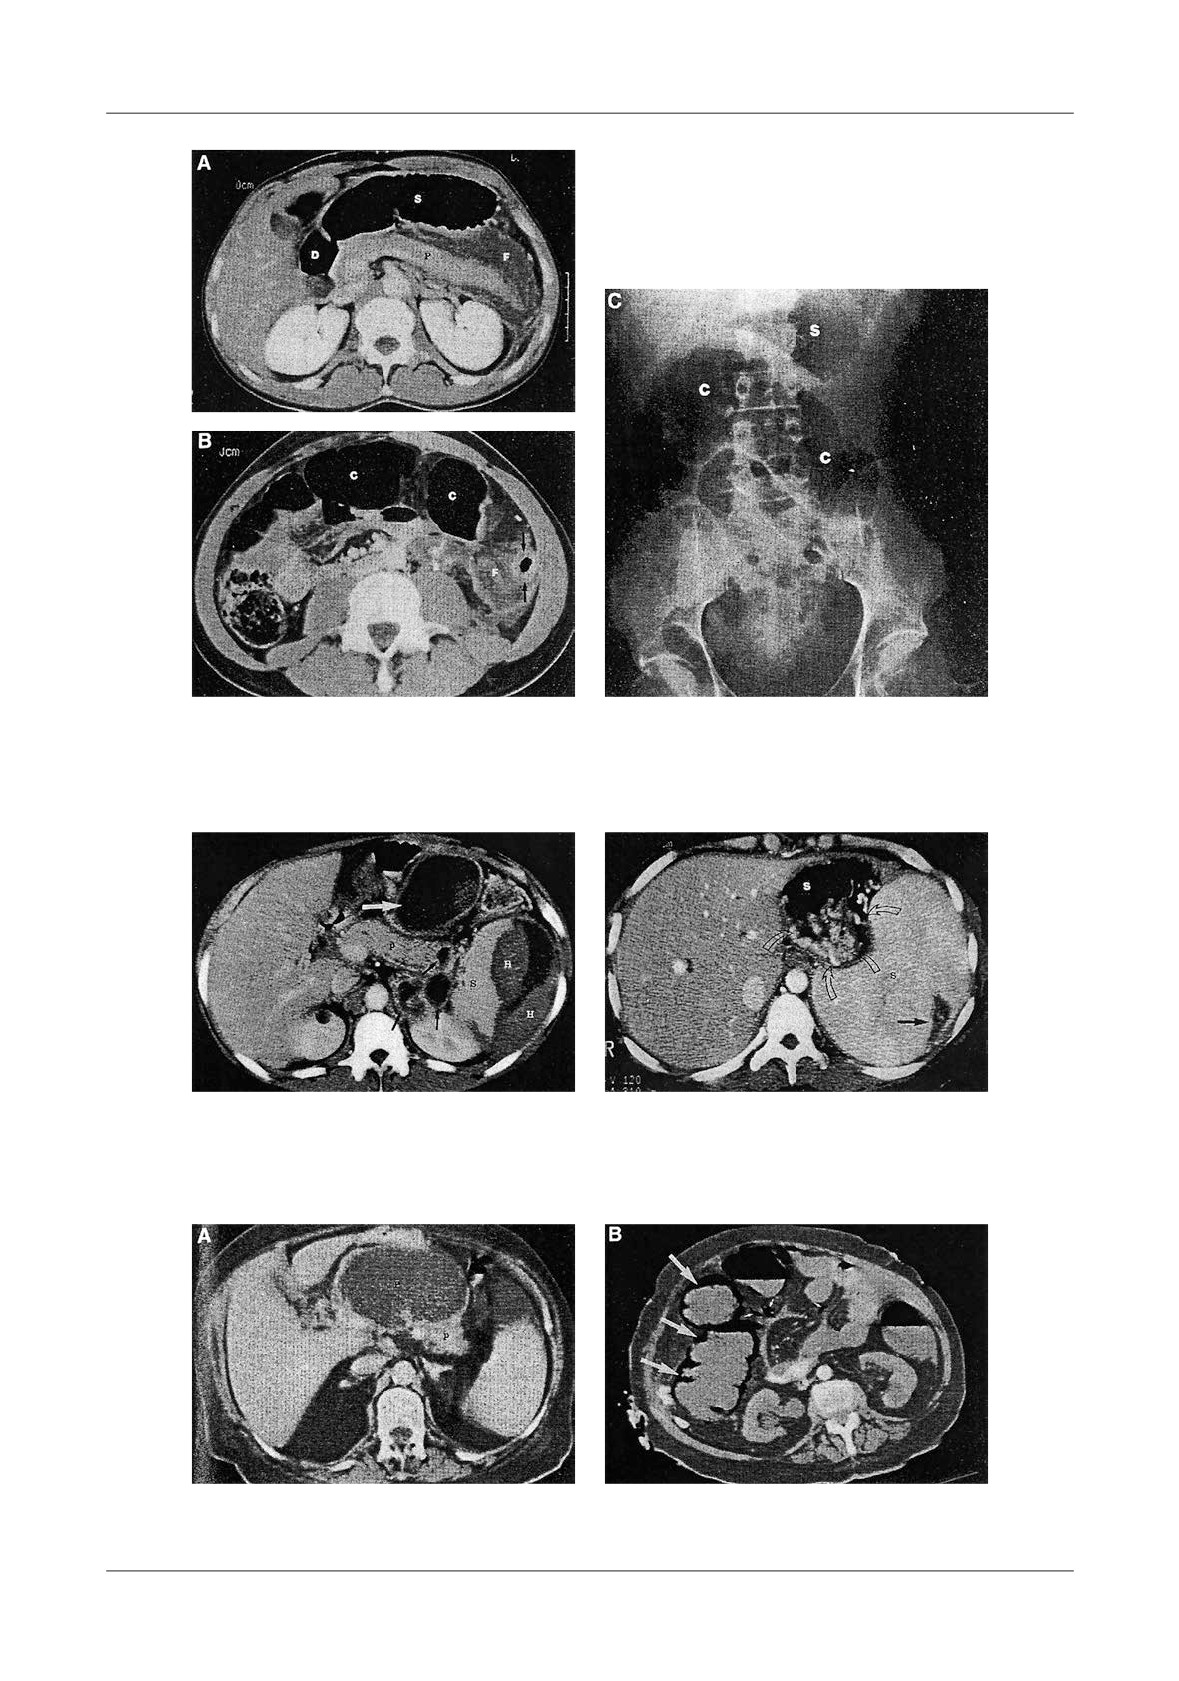

Figure 1. Pancreatic necrosis with the development of a pseudocyst, ileus and colonic in ltration in a 38

-year-old man. A-At admission the CT- shows enlarged pancreas and peripancreatic in ammation,  uid

(N=necrosis, P=pancreas, S=stomach), B-Lique ed necrosis nine days later with partially encapsulated

uid collection in the lesser sac, C-Dilated small bowel loops, with a haustral transverse colon. S=small

bowel, T=transverse colon, D-Five weeks later, fully encapsulated pseudocyst in the lower sac, with

lique ed necrosis in the neck of the pancreas (D=duodenum, N=necrosis, P=pseudocyst, S=stomach)

necrotic tissue (Figure 1).

Figure 4. Pancreatic pseudocyst secondary to necrosis.

A - Liquefaction necrosis in the tail, B - Large pseudocyst bulging into the stomach

Figure 5. Pseudocyst communicating with  the pancreatic duct, A-With CT image of enlarged gland

and peripancreatitis, B-After discharge from hospital, 2 weeks later, CT shows a residual collection,

C-6 months later, the patient had abdominal pain, CT shows an enlarging pseudocyst,

D-Trans gastric punction with  stulography, shows communication with the Wirsung duct

Figure 6. A - Normally enhancing pancreas with peripancreatic  uid collections (D=duodenum,

S=stomach, F= uid, P=pancreas), B - Transverse colon is air  lled and distended, C - Native

abdominal  lm showing distension of transverse colon

Figure 7. Intrasplenic and subcapsular

Figure 8. Splenomegaly and gastric varices with

hemorrhage (H=hemorrhage, S=spleen,

two episodes of pancreatitis. Massive enlarged

P=pancreas)

spleen, with peripheral infarct

Figure 9. Infarcted right colon in A.P. A-CT image shows pseudocyst with pancreatic necrosis

6 weeks following AP, B-One month later CT showed late pneumocystosis